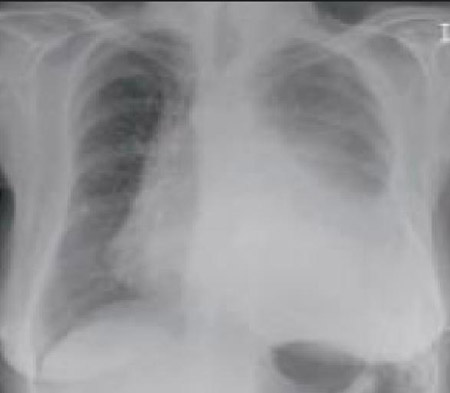

Chest x-ray

A chest x-ray should be obtained early in the evaluation of chronic cough.[38] Although it is not diagnostic of the most common causes, findings may quickly divert the evaluation to causes of greater gravity, such as structural lung diseases. These include lung cancer, pulmonary fibrosis, tuberculosis, bronchiectasis, pneumonia, aspiration, and sarcoidosis.[Figure caption and citation for the preceding image starts]: Chest x-ray showing hyperinflation in a patient with COPD. The hyperinflation is caused by the emphysema component of COPD, rather than the chronic bronchitis that underlies symptoms of coughFrom the personal collection of Dr M. A. Sharifabadand, SUNY at Stony Brook School of Medicine, Department of Pulmonary and Critical Care Medicine, Mineola, New York and Dr J. P. Parsons, The Ohio State University Medical Center, Columbus; used with permission [Citation ends].com.bmj.content.model.assessment.Caption@65a65855[Figure caption and citation for the preceding image starts]: Chest x-ray showing multiple miliary lung metastases (arrows). The primary tumour was a thyroid carcinomaE. Dick, Student BMJ. 2001;9:10-12 [Citation ends].com.bmj.content.model.assessment.Caption@25657fee[Figure caption and citation for the preceding image starts]: Chest x-ray showing left hilar carcinoma (arrow)From: E. Dick, Student BMJ. 2000;8:358-360 [Citation ends].com.bmj.content.model.assessment.Caption@567b9fef[Figure caption and citation for the preceding image starts]: Chest x-ray showing a cavitating right hilar carcinoma (arrow)E. Dick, Student BMJ. 2001;9:10-12 [Citation ends].com.bmj.content.model.assessment.Caption@3d6fa55[Figure caption and citation for the preceding image starts]: Chest x-ray in a patient with bronchogenic carcinoma showing a left-sided pleural effusionFrom: R. Thakkar, Student BMJ. 2001;9:458 [Citation ends].com.bmj.content.model.assessment.Caption@5b46acec[Figure caption and citation for the preceding image starts]: Chest x-ray showing interstitial fibrosis in a patient with amiodarone pulmonary toxicityFrom the personal collection of Dr A. Pataka and Professor P. Argyropoulou, Aristotle University, Thessaloniki, Greece; used with permission [Citation ends].com.bmj.content.model.assessment.Caption@2c3c94b0[Figure caption and citation for the preceding image starts]: Chest x-ray showing pulmonary tuberculosis with cavitationFrom the personal collection of Dr M. Narita, Department of Pulmonary and Critical Care Medicine, University of Washington [Citation ends].com.bmj.content.model.assessment.Caption@3dd7f84b[Figure caption and citation for the preceding image starts]: Chest x-ray showing multiple discrete nodules throughout both lungs (one of which is circled) in a patient with miliary tuberculosisE. Dick, Student BMJ. 2001;9:10-12 [Citation ends].com.bmj.content.model.assessment.Caption@23fa6365[Figure caption and citation for the preceding image starts]: Chest x-ray with lack of normal tapering producing a tram line in a patient with bronchiectasisFrom the personal collection of Dr S.M. Bhorade, University of Chicago Medical Center; used with permission [Citation ends].com.bmj.content.model.assessment.Caption@36b415f2[Figure caption and citation for the preceding image starts]: Chest x-ray with dilated and thickened airways in a patient with bronchiectasisFrom the personal collection of Dr S.M. Bhorade, University of Chicago Medical Center; used with permission [Citation ends].com.bmj.content.model.assessment.Caption@78e208fa[Figure caption and citation for the preceding image starts]: Chest x-ray showing increased opacification of the right perihilar region and superior segment of the right lower and upper lobes consistent with worsening aspiration pneumoniaFrom the personal collection of Dr R. Kanner, University of Utah School of Medicine [Citation ends].com.bmj.content.model.assessment.Caption@71be2c1f[Figure caption and citation for the preceding image starts]: Portable chest x-ray with bibasilar opacities, worse on the right than the left, in a patient with hospital-acquired pneumoniaFrom the personal collection of Dr F. W. Arnold, Division of Infectious Diseases, Department of Medicine, University of Louisville School of Medicine [Citation ends].com.bmj.content.model.assessment.Caption@2c704497[Figure caption and citation for the preceding image starts]: Chest x-ray showing early ill-defined opacities of the right upper lobe above the minor fissure consistent with early changes of aspiration pneumoniaFrom the personal collection of Dr R. Kanner, University of Utah School of Medicine [Citation ends].com.bmj.content.model.assessment.Caption@23fa54d0[Figure caption and citation for the preceding image starts]: A. Portable upright chest x-ray before aspiration; B. Chest x-ray 1 hour after aspiration, showing bilateral diffuse alveolar infiltrates, worse at the bases on the right sideFrom the personal collection of Dr S. Murgu and Dr H. Colt, University of California at Irvine Medical Center [Citation ends].com.bmj.content.model.assessment.Caption@7860be3a[Figure caption and citation for the preceding image starts]: Chest x-ray showing bilateral hilar adenopathy in a patient with sarcoidosisFrom the personal collection of Dr M.P. Muthiah, Division of Pulmonary and Critical Care and Sleep Medicine, University of Tennessee [Citation ends].com.bmj.content.model.assessment.Caption@31e94b4e